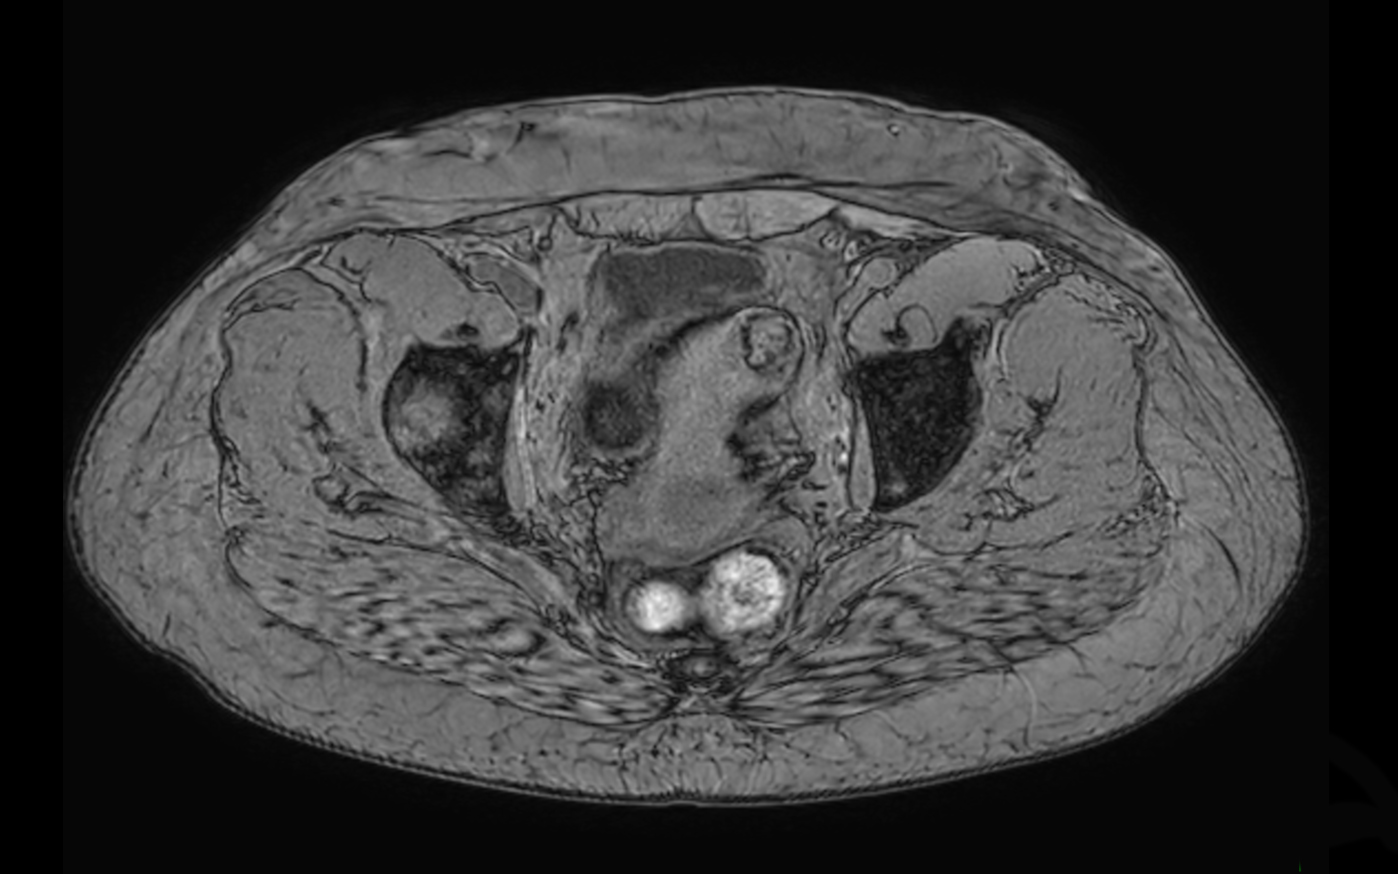

Axial T1w TSE